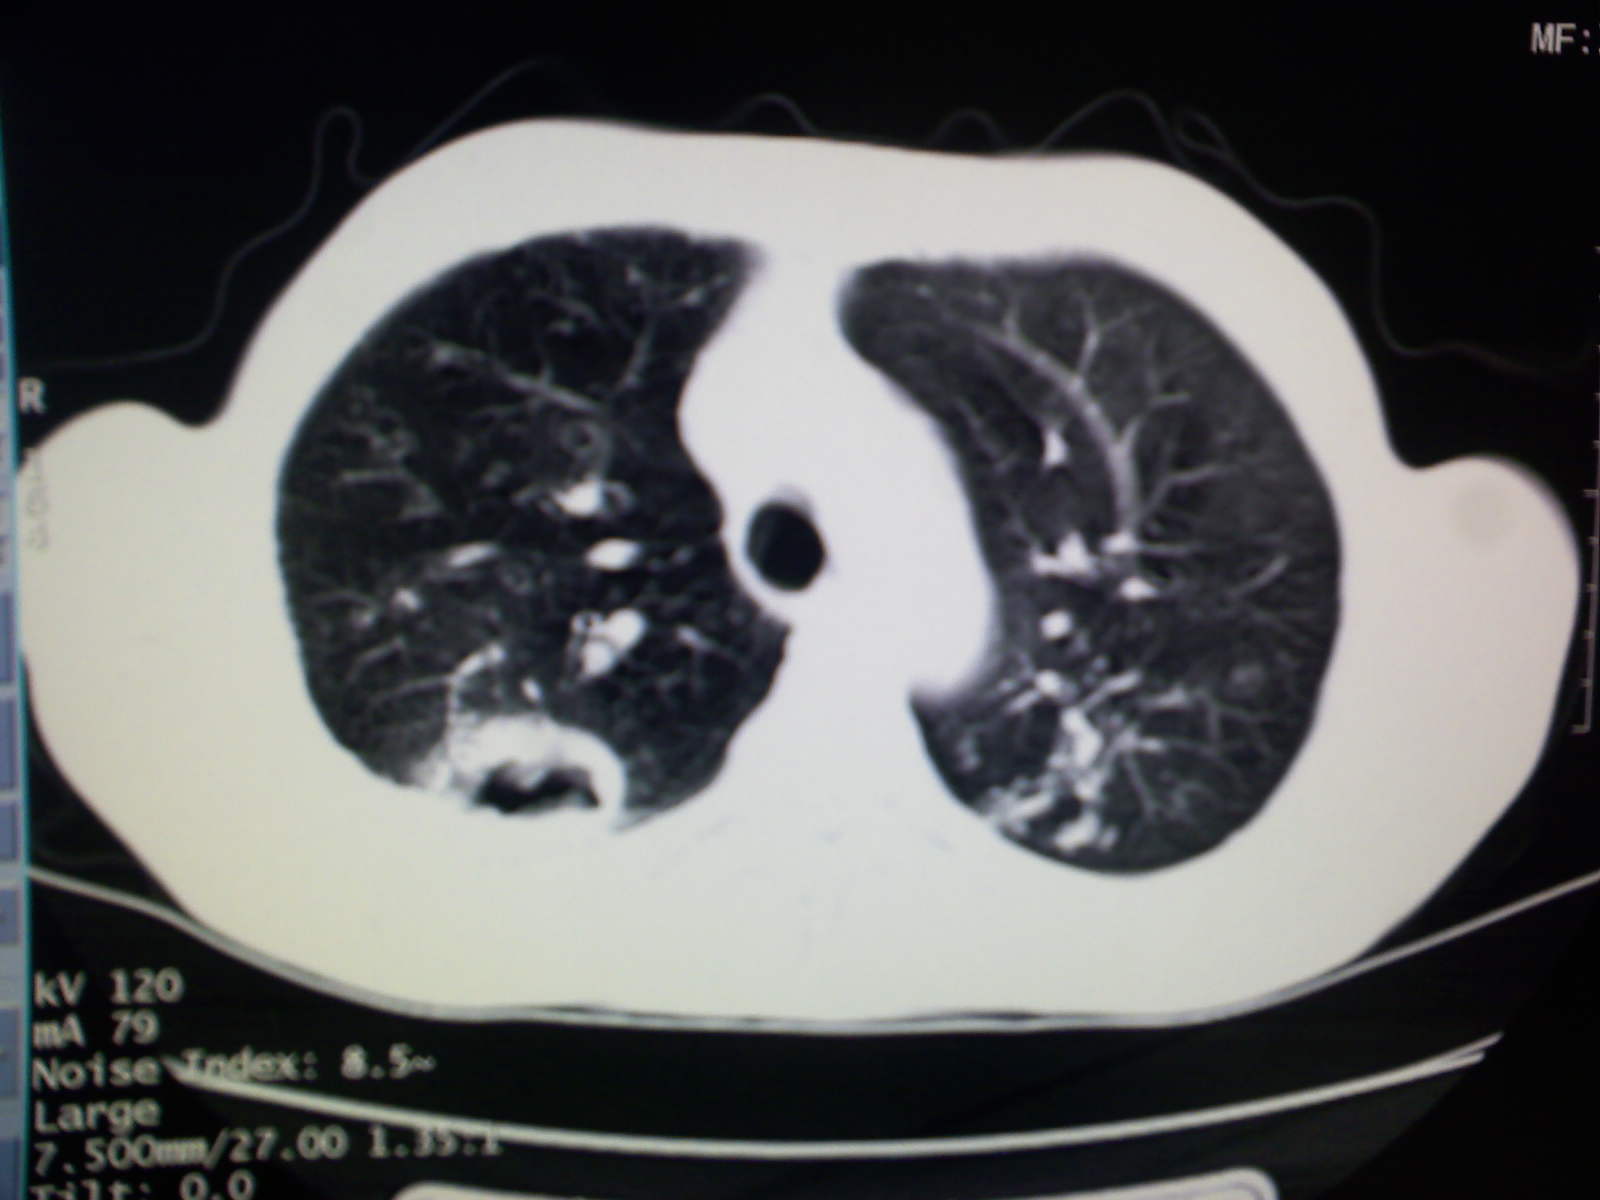

以下是引用卜一在2009-4-11 15:50:00的发言:[br]双肺继发性肺结核伴空洞形成,不排除合并霉菌感染!(病灶呈多形态 多特征 散在分布)。另:合并支气管扩张征伴感染!

以下是引用主力军在2009-4-11 15:55:00的发言:[br]两肺继发性肺结核可能性大。

以下是引用康鹏在2009-4-11 16:30:00的发言:[br]双肺继发性肺结核伴空洞形成合并感染[br]支气管扩张合并感染